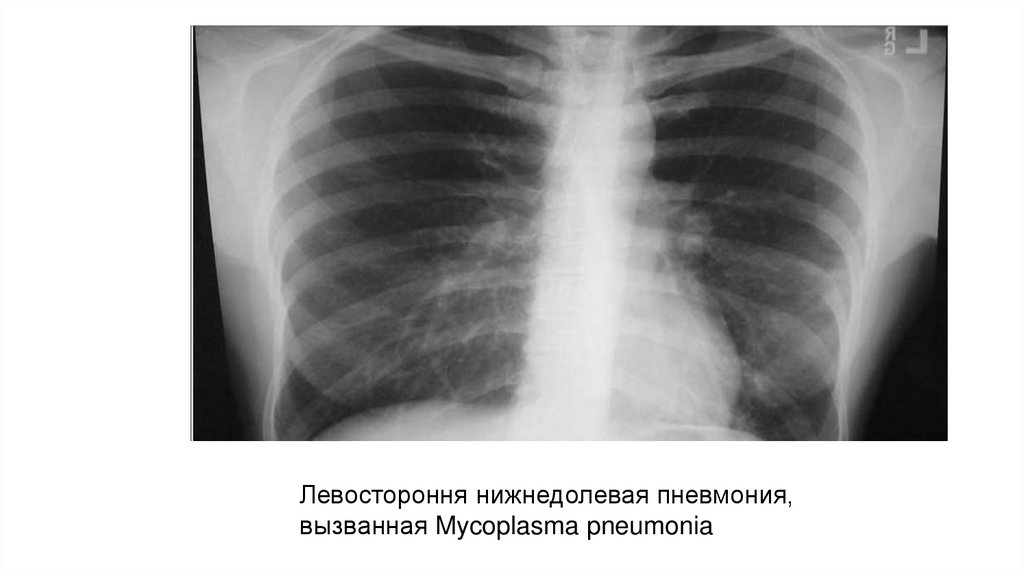

Левостороння нижнедолевая пневмония,

вызванная Mycoplasma pneumonia